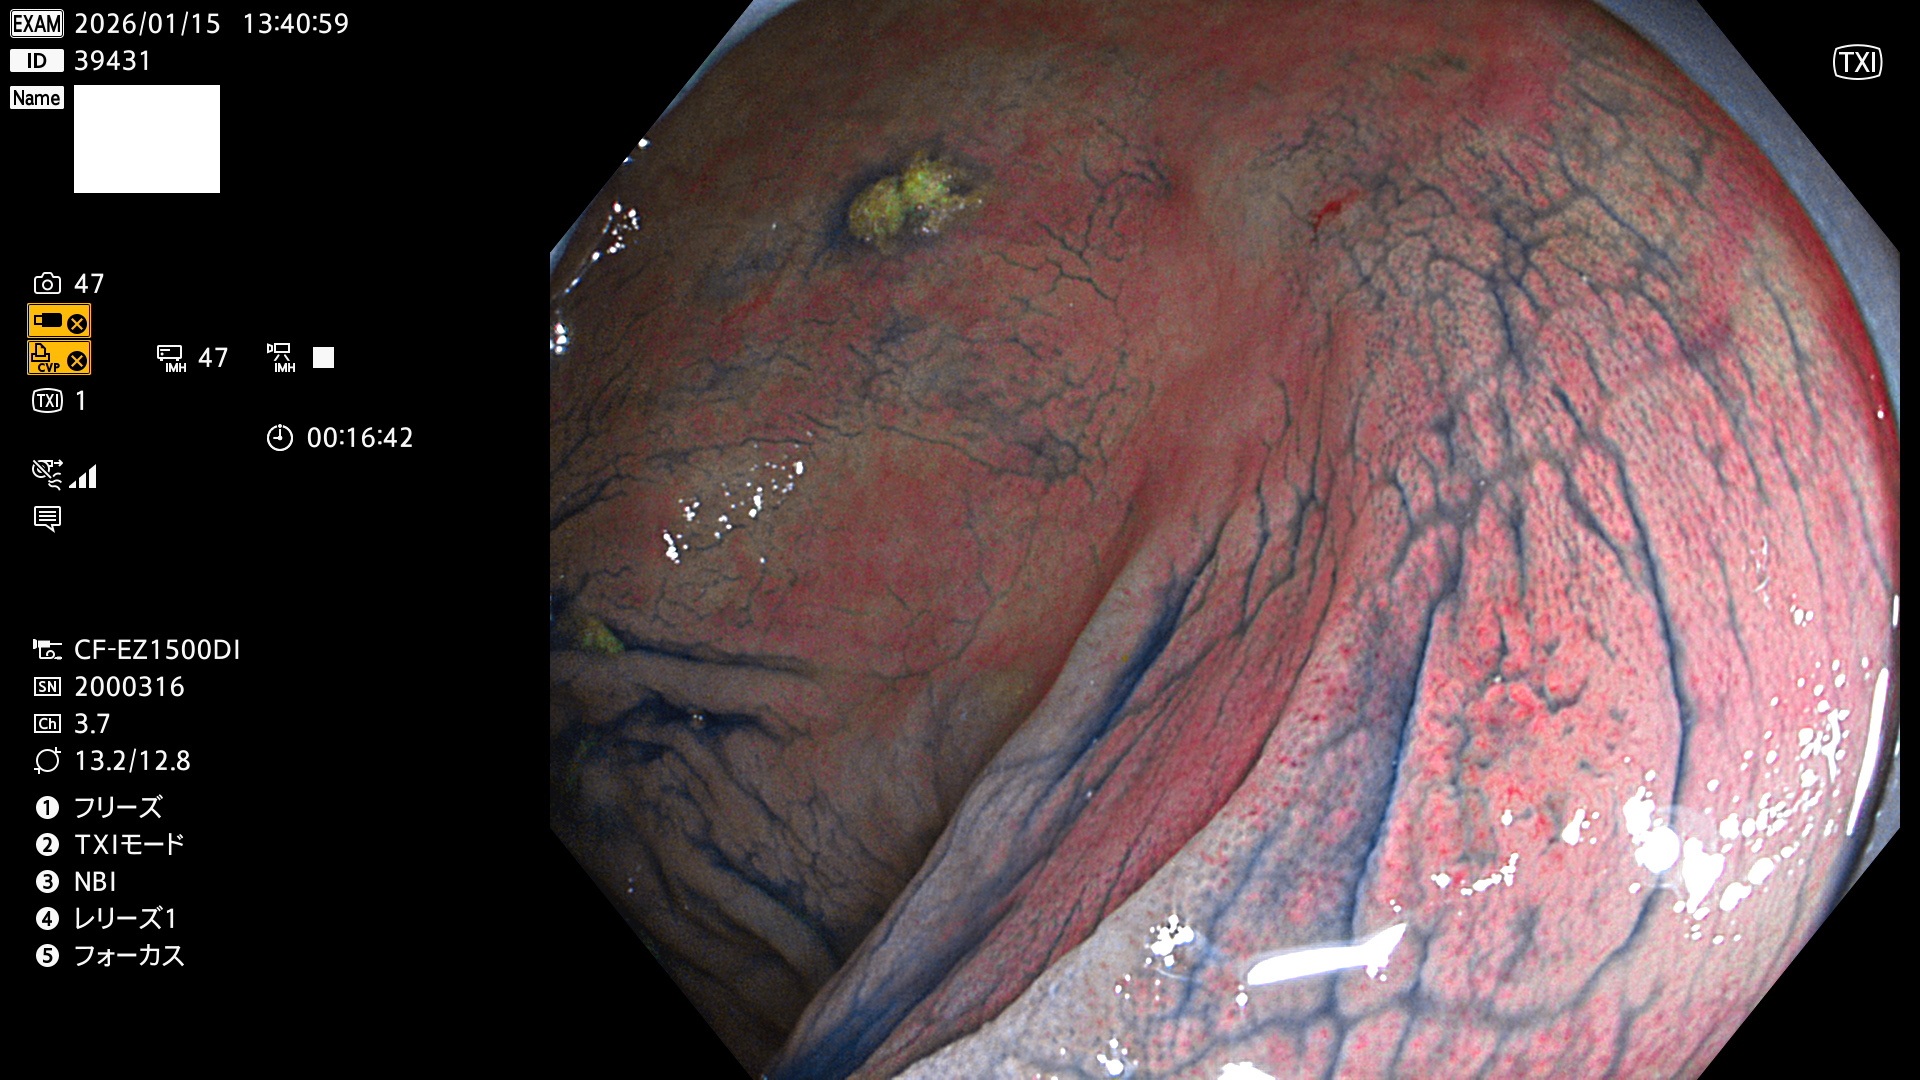

完全に平坦な物をUb、陥凹している物をUcと呼びます。Ubは認識が困難で、Ucはびらん(炎症)と紛らわしいために見落とされやすく、「内視鏡後・大腸癌」の原因になります。

毎週の検査(木・金・土・日)に発見されたUbとUc型・腺腫を、その週の日曜の夜にUPし1週間、提示します。

2026年1月15日〜1月18日の4日間(40件)5個 (Uc_ADR=5個/40人=13%)